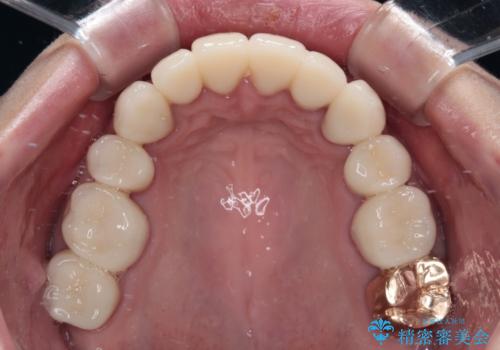

矯正治療終了後に、残った歯をオールセラミッククラウンにて補綴治療を行うこととしました。

途中来院が困難な時期があったり、歯周外科処置を行って治癒を待ったりと、治療期間は長くなりましたが、初診時とは比べものにならないくらいきれいに仕上げることができました。